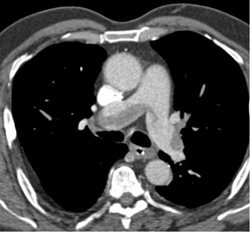

Right Sided Arch and Aberrant Left Subclavian Artery